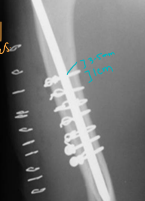

Tibia & fibula Fractures

Considerations: Common, Min soft tissue envelope, risk of open fracture

fibula broke concurrently, not broke in young

Tx:

Rx: Casting/splinting

closed, transverse fractures, >50% reduction, lateral splint (greenstick fractures)

Sx: Plate + screws, IM pin + cerclage, Interlocking nail, ESF

Avulsion: tension band + K-wire, or K-wires alone

Physeal: urgent fixation, cross pins

younger animals